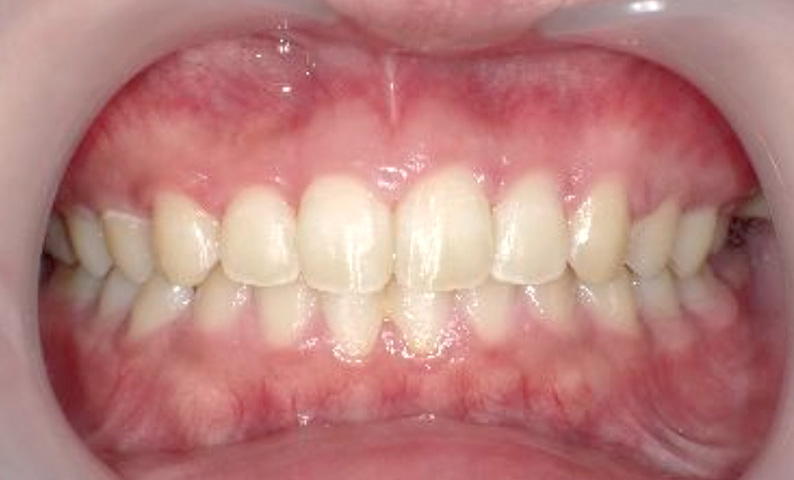

症例_004 上下顎の部分矯正

治療期間:8ヶ月金額:54万円+税女性前歯のガタガタ捻転歯

| Before | After |